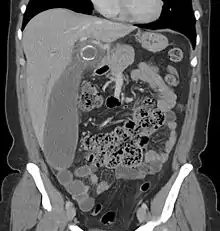

In children the clinical examination is important to determine which children with abdominal pain should receive immediate surgical consultation and which should receive diagnostic imaging.[42] Because of the health risks of exposing children to radiation, ultrasound is the preferred first choice with CT scan being a legitimate follow-up if the ultrasound is inconclusive.[43][44][45] CT scan is more accurate than ultrasound for the diagnosis of appendicitis in adults and adolescents. CT scan has a sensitivity of 94%, specificity of 95%. Ultrasonography had an overall sensitivity of 86%, a specificity of 81%.[46]

Computed tomography

Where it is readily available, computed tomography (CT) has become frequently used, especially in people whose diagnosis is not obvious on history and physical examination. Although some concerns about interpretation are identified, a 2019 Cochrane review found that sensitivity and specificity of CT for the diagnosis of acute appendicitis in adults was high.[51] Concerns about radiation tend to limit use of CT in pregnant women and children, especially with the increasingly widespread usage of MRI.[52][53]

The accurate diagnosis of appendicitis is multi-tiered, with the size of the appendix having the strongest positive predictive value, while indirect features can either increase or decrease sensitivity and specificity. A size of over 6 mm is both 95% sensitive and specific for appendicitis.[54]

However, because the appendix can be filled with fecal material, causing intraluminal distention, this criterion has shown limited utility in more recent meta-analyses.[55] This is as opposed to ultrasound, in which the wall of the appendix can be more easily distinguished from intraluminal feces. In such scenarios, ancillary features such as increased wall enhancement as compared to adjacent bowel and inflammation of the surrounding fat, or fat stranding, can be supportive of the diagnosis. However, their absence does not preclude it. In severe cases with perforation, an adjacent phlegmon or abscess can be seen. Dense fluid layering in the pelvis can also result, related to either pus or enteric spillage. When patients are thin or younger, the relative absence of fat can make the appendix and surrounding fat stranding difficult to see.[55]